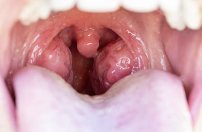

1. 오른쪽 편도선염 – 가장 흔한 국소 통증 원인

편도선은 목 안쪽 좌우에 있는 면역기관이에요.

세균 감염이나 피로, 면역력 저하로 오른쪽 편도에만 염증이 생길 수 있고,

이때는 침을 삼킬 때 오른쪽에만 찌릿하거나 쿡 찌르는 느낌이 들어요.

의심 증상

- 침 삼킬 때 오른쪽 목만 아픔

- 오른쪽 목구멍이 붓고 붉어짐

- 편도선 위쪽에 흰 점 또는 고름

- 턱 아래가 눌리면 아픔

- 열 동반 (38.5도 이상)

자가 확인법

거울로 입을 벌리고 목 안쪽을 보면, 오른쪽 편도가 왼쪽보다 부어 있고 충혈되었다면 편도선염 가능성이 높아요.